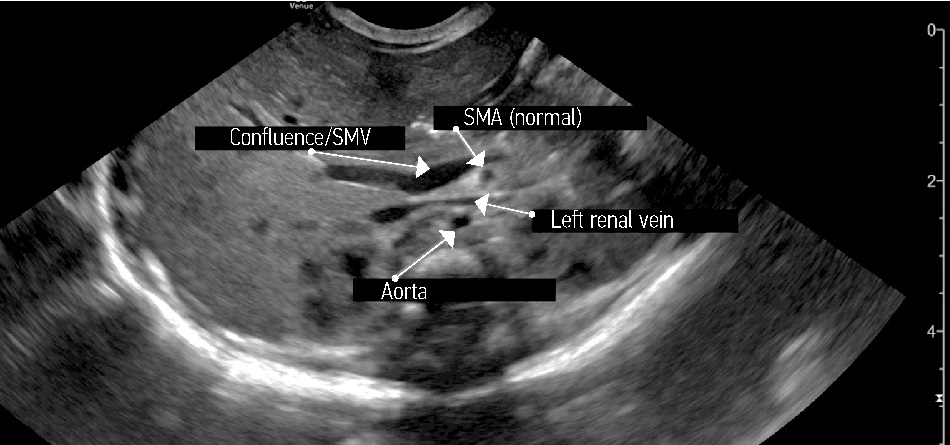

У двоих детей отсутствовали ультразвуковые признаки, указывавшие на мальротацию. В одном случае взаиморасположение мезентериальных сосудов представлялось типичным (рис. 4), во втором получена информация только о наличии жидкости и расширенных петлях кишечника.

Рис. 4. Нормальное расположение мезентериальных сосудов у новорожденного, В-режим

Fig. 4. Normal location of mesenteric vessels in a newborn, B-mode